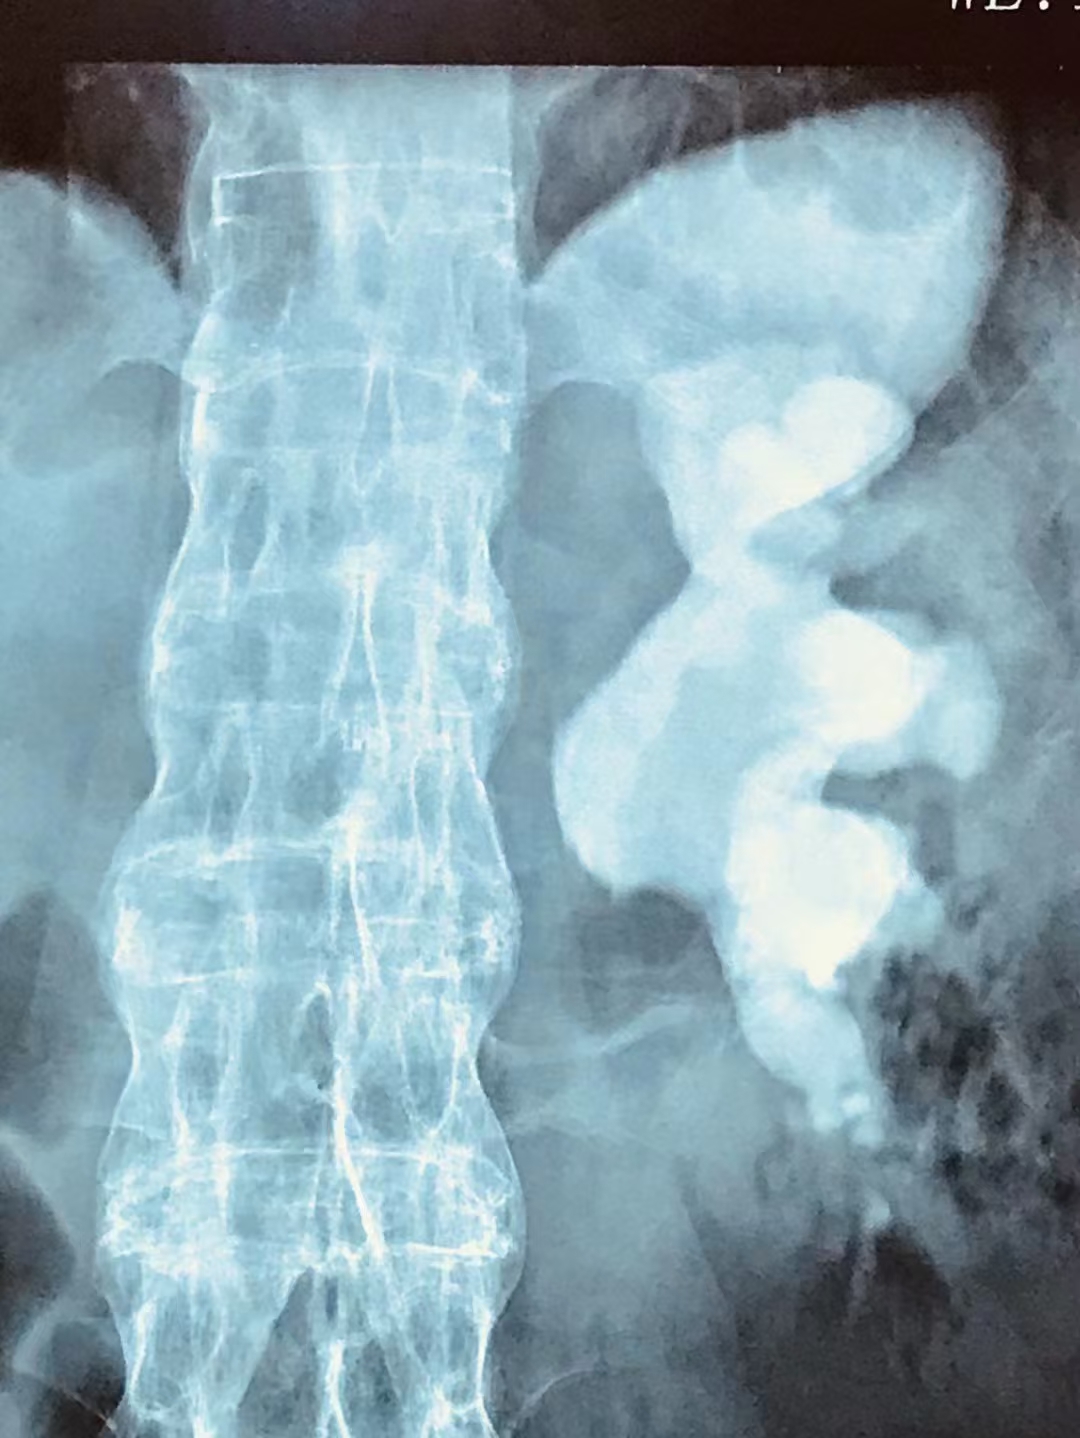

“左输尿管上段结石2.1*0.8cm;左肾铸型结石(最大直径4.9cm)、重度积水、肾功能严重损伤;右肾多发结石(最大直径2.1cm)、右肾轻度积水。”47岁的李先生坐在云南结石病医院泌尿外科的病房里,呆呆的看着自己的检查报告。